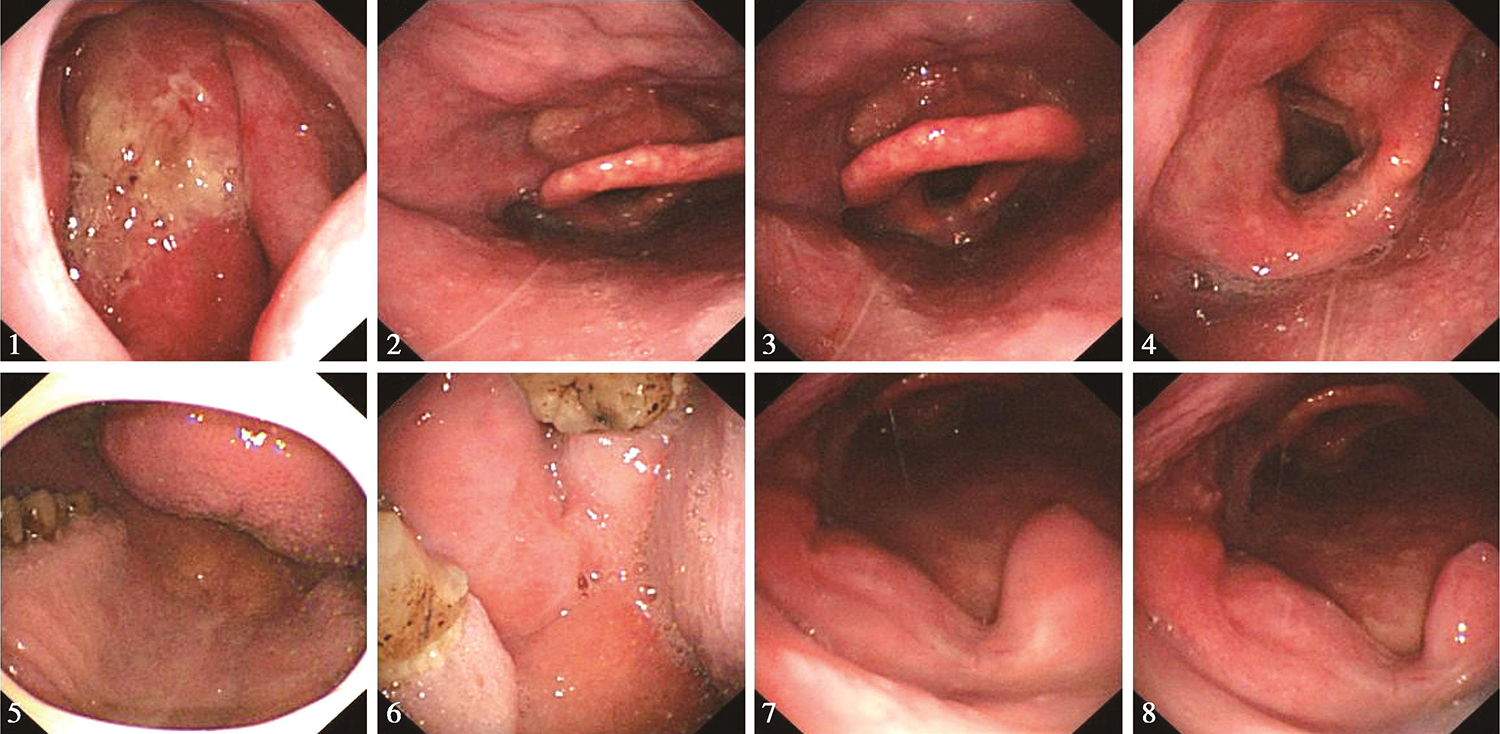

2.2016年10月8日电子鼻咽喉镜

鼻腔进镜顺利。鼻咽部结构完整,黏膜光滑,未见明显异常。经口观察,硬腭基本平整,左侧磨牙后区及左侧软腭和腭舌弓可见溃疡型肿物(活检)(图2),与邻近舌根关系密切,左侧扁桃体处可见溃疡,可疑侵及。口咽右侧壁未见明显异常。舌根部基本平整。下咽及喉部结构完整,未见明显异常。声带活动正常。

图1颈胸部CT示双侧扁桃体饱满,边界欠清楚

图2电子鼻咽喉镜见左侧磨牙后区及左侧软腭和腭舌弓可见溃疡型肿物

内镜诊断:

口咽左侧壁肿物(性质待病理检查),考虑为癌,侵及左侧磨牙后区。

(2)2016年12月13日电子内镜检查:口咽癌放疗23次复查,鼻腔进镜顺利。鼻咽部黏膜充血,表面平整,可见有分泌物。经口观察,左侧磨牙后区肿物较前消退明显,局部仍显肿胀,不平整。左侧扁桃体区肿物较前消退明显,较前变平,略显隆起(图7)。软腭水肿明显。下咽及喉部未见明显异常。声带活动正常。

内镜诊断:口咽癌放疗中,左侧磨牙后区及左侧扁桃体区肿物较前消退明显,现可见略隆起。

图7电子内镜见口咽左侧壁肿物较前缩小

1)2017年1月11日电子内镜检查:

口咽癌放疗末复查,鼻腔进镜顺利。鼻咽部有分泌物,黏膜略充血,未见明显异常。经口观察,左侧磨牙后区基本变平,略肿胀。左侧扁桃体处肿物似消退,肿瘤已不具体(图8)。舌根部基本平整。下咽及喉部未见明显异常。声带活动正常。

内镜诊断:口咽癌放疗末,左侧磨牙后区和左侧扁桃体处肿物已不具体,基本变平,注意随诊。

图8电子内镜见左侧扁桃体处肿物似消退

2.2017年3月17日电子内镜检查

口咽癌放疗后2月余复查,鼻腔进镜顺利。鼻咽部结构完整,黏膜光滑,未见明显异常。经口观察,硬腭及软腭光滑,左侧扁桃体区基本平整,未见明显肿瘤征象(图11)。舌根部淋巴滤泡略增生。下咽及喉部黏膜略水肿,声带活动正常。内镜诊断:口咽癌放疗后,口咽左侧壁基本恢复平整,未见明显肿瘤征象。

图11口咽癌放疗后电子内镜口咽左侧壁基本恢复平整